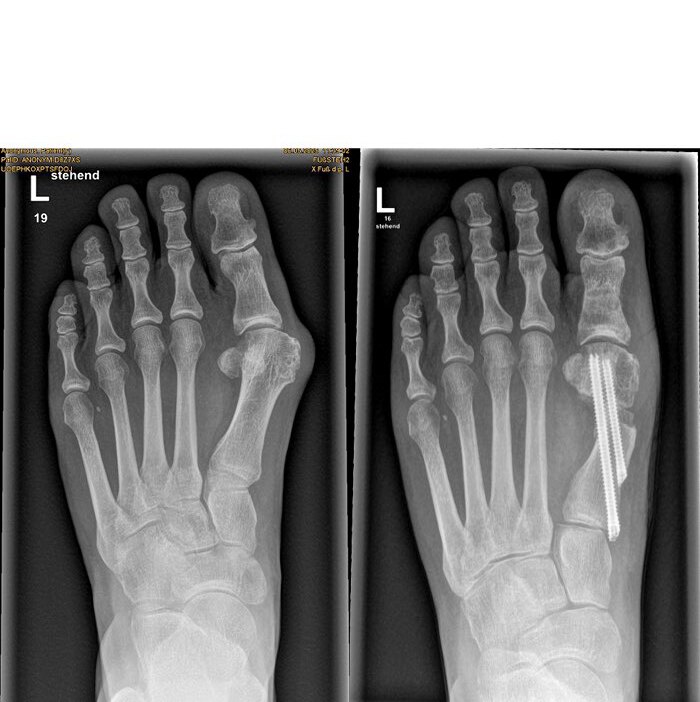

Es gibt unterschiedliche OP-Methoden zur Behandlung der Fehlstellung – von der Entfernung des Knochenvorsprungs über eine Umstellung des Mittelfußknochens bis hin zu einer Versteifungsoperation. Dr. Mann erklärt die neue Methode: »Mithilfe filigraner Werkzeuge, die wir durch vier millimeterkleine Schnitte einführen, durchtrennen wir den Mittelfußknochen unterhalb des Großzehengelenks. Wir verschieben das Köpfchen zur Mitte und fixieren es mit zwei speziell für dieses Verfahren hergestellten, abgeschrägten Schrauben. Abschließend wird der überstehende Knochen außen entfernt.« All dies geschieht unter Röntgensicht.

Die Vorteile der sogenannten MICA-Methode (Minimalinvasive Chevron-/Akin-Osteotomie): »Man muss das Gelenk nicht öffnen, benötigt keine größeren Hautschnitte und die Rehabilitationszeit ist viel geringer als nach einer herkömmlichen OP. Gleichzeitig gibt es weniger Schmerzen, Narben und Wundheilungsprobleme«, so der Facharzt. Ute Pacher erhält nach der OP zunächst einen Spezialschuh – ihren Fuß darf sie gleich wieder belasten. Sechs Wochen später trägt sie bereits wieder ihre eigenen Schuhe.